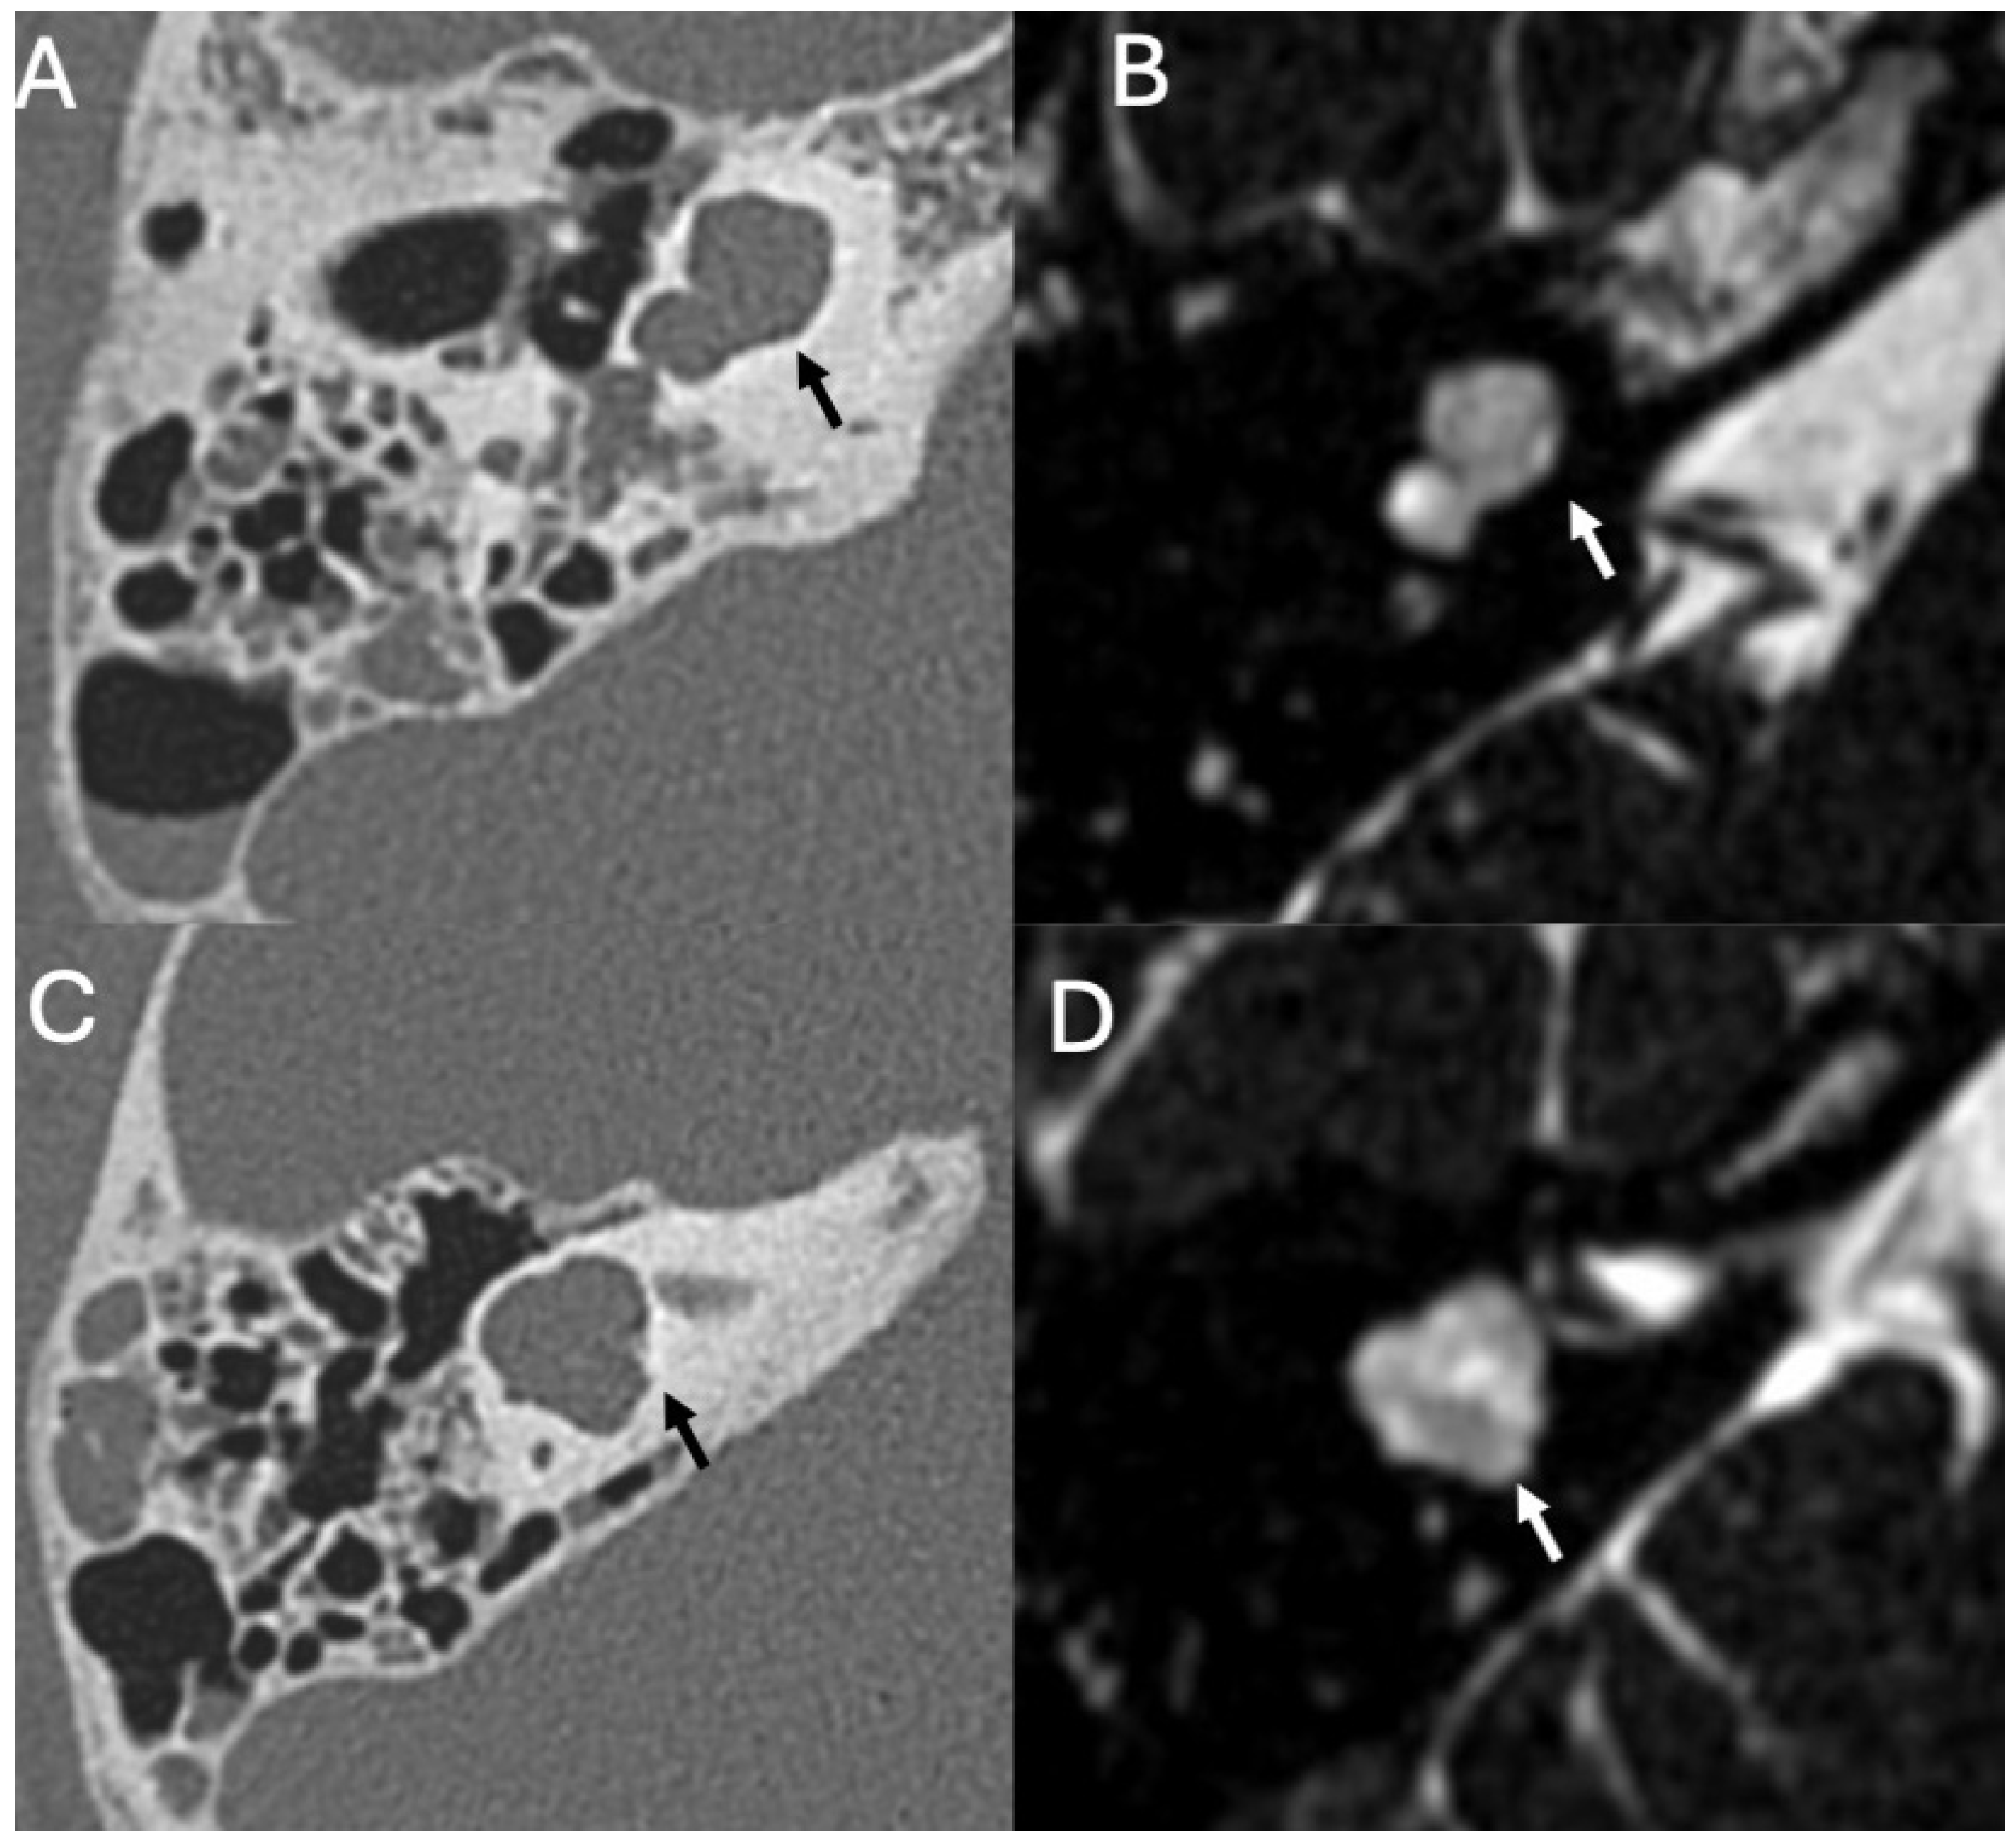

3.3.1. Imaging

3.3.2. Complications

| Cholesteatoma and Otogenic Complications | Kuo et al., 2015 [26]; Baráth et al., 2011 [27]; Mustafa et al., 2014 [28]; Dubey et al., 2010 [29]; Sun et al., 2014 [30]; Lee et al., 2020 [31] | Reviews and retrospective studies | Cholesteatoma causes erosion and CSF leak, leading to meningitis (12–30% incidence); MRI improves detection; pediatric risk emphasized. |